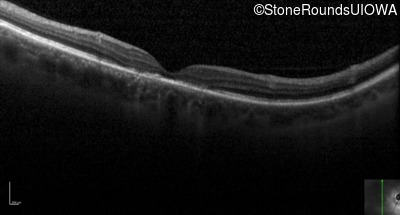

Optical Coherence Tomography - Left - 20/100 sc

Exemplar / OCT Stack